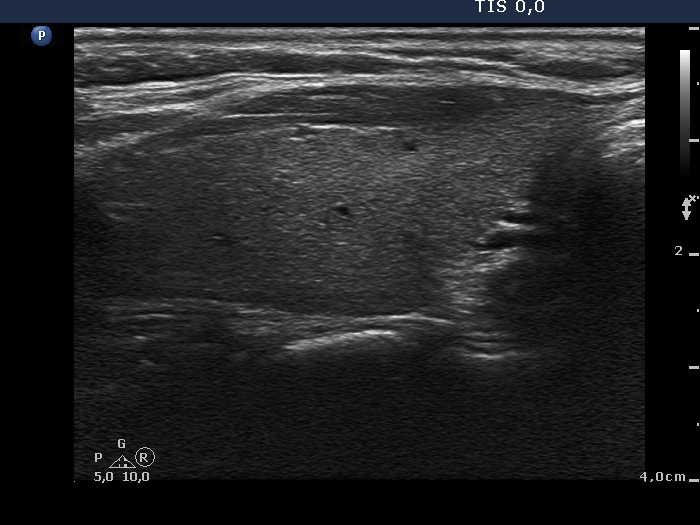

Ultrasonography. The right thyroid was moderately hypoechogenic without any circumscribed lesions. The left thyroid was removed. There were several enlarged lymph nodes in the right submandibular area. The largest one presented two discrete, more hypoechogenic intranodal lesions and a regular hilum.